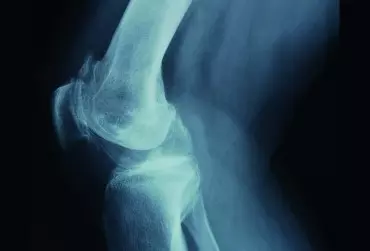

Palpacja stawu łokciowego

Dotyk umożliwia badanie i rozpoznawanie wielu struktur ciała. Można w ten sposób ocenić ich rozmiar, kształt, twardość oraz położenie. Jest to podstawowe narzędzie w dziedzinie anatomii palpacyjnej, która – z racji swojej specyfiki – jest nierozerwalnie związana z praktyką.